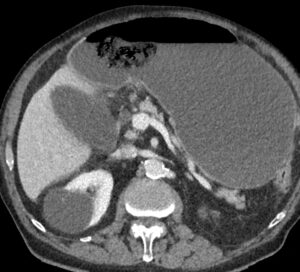

TC axial con contraste IV en fase portal.